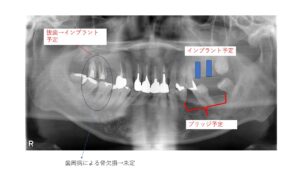

最初にざっと以下のような計画を立てました。

スプリントで顎位を確認しましたが、大きな変化は見られませんでした。なので、先に臼歯部の咬合を作っていくことにしてインプラントの埋入をすすめていきました。

左上はデジタルでガイドを作って埋入

右上は骨のある5番目の歯にはすぐに埋入できましたが、奥は抜歯したら骨が残ってなくて骨を造ることから始めました。上が抜歯後すぐで下がGBRしたあとです。